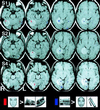

Studies of patients with focal brain damage suggest that topographical representation is subserved by dissociable neural subcomponents. This article offers a condensed review of the literature of "topographical disorientation" and describes several functional MRI studies designed to test hypotheses generated by that review. Three hypotheses are considered: (i) The parahippocampal cortex is critically involved in the acquisition of exocentric spatial information in humans; (ii) separable, posterior, dorsal, and ventral cortical regions subserve the perception and long term representation of position and identity, respectively, of landmarks; and (iii) there is a distinct area of the ventral occipitotemporal cortex that responds maximally to building stimuli and may play a role in the perception of salient landmarks. We conclude with a discussion of the inferential limitations of neuroimaging and lesion studies. It is proposed that combining these two approaches allows for inferences regarding the computational involvement of a neuroanatomical substrate in a given cognitive process although neither method can strictly support this conclusion alone.